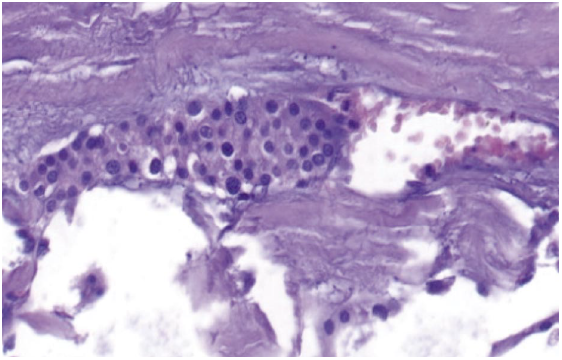

При микроскопическом исследовании опухоль с крупными кистозными полостями. Стенки кист представлены опухолевой тканью, формирующей солидные, ацинарные и трабекулярные структуры из главных клеток (рис. 9). Опухолевые клетки мелкого и среднего размера с округлыми и овальными ядрами, светлой и слабоэозинофильной цитоплазмой. Ядерный полиморфизм выражен слабо с наличием мелких очагов опухолевых клеток с умеренно полиморфными ядрами. Фигуры митозов и очаги некрозов не визуализируются. Опухоль окружена фиброзной капсулой с наличием в области утолщения множественных участков грибовидной капсулярной инвазии и очагов инвазивного роста в прилежащую жировую клетчатку (рис. 10). Также обнаружены признаки сосудистой инвазии (рис. 11).

Рис. 11. Рак паращитовидной железы. Опухолевые комплексы в просвете мелкого венозного сосуда. Окраска гематоксилин-эозином, ×200.

Fig. 11. Parathyroid cancer. Tumor complexes in the lumen of a small venous vessel. Hematoxyline-eosine staining, ×200.